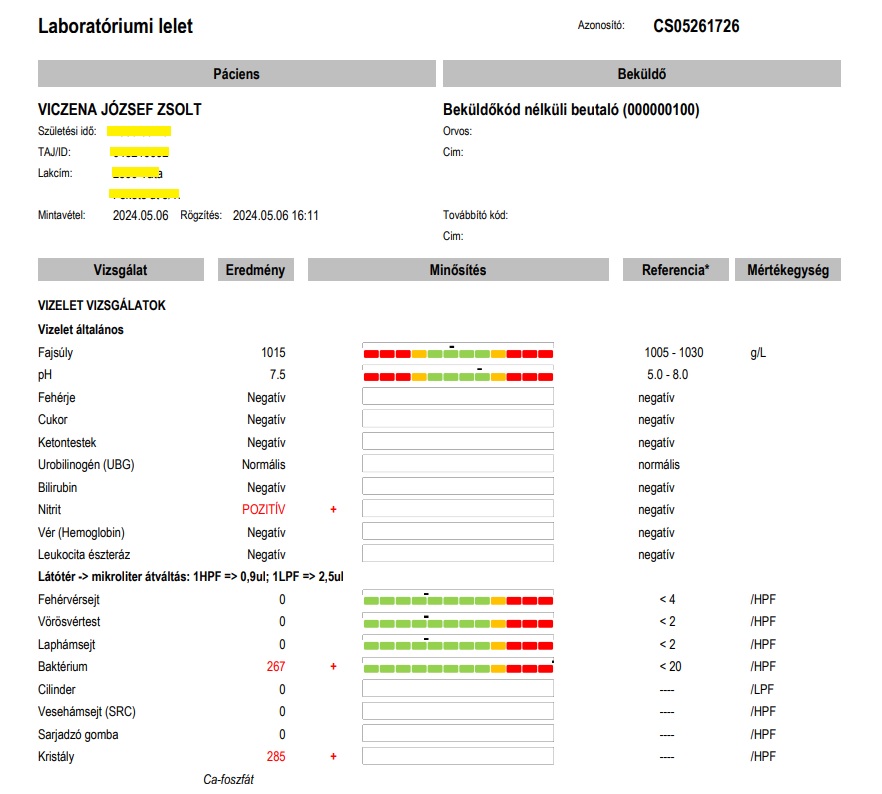

Na ez a másik véglet. Az antiorvos, aki pánikba esik egy lelettől (na nem csak lelettől, hanem a súlyos felelősség terhétől). Hát kérem, ez olyan groteszk volt, hogy el nem hinné senki, hogy ilyen létezik. De ketten láttuk a fiammal. Tudtuk, hogy egy ilyen intézménybe a fiam nem léphet be többé. A magyar egészségügyben nincs lehetetlen! Közben a fiam vesefertőzése, vesemedence-gyulladása több mint 3 hónapja nem volt kezelve. A fenti leleten a Nitrit is jelzett, ami a fertőzés egyik legfontosabb markere és a vizelet tele volt baktériummal is! De a kezelőorvos elfutott… és bár előtte még felírta Zsolt telefonszámát, hogy visszahív minket a kezeléssel, befekvéssel kapcsolatban (80 nap késéssel az első nagy vérvizeléshez képest!!!), a hívás nem történt meg! Soha!

Később, júliusban Zsolt új háziorvosa beutalója által készült 24 órás vizeletgyűjtés is, amelynek eredménye közel 2-szeres összfehérje szintet mutatott a vizeletben a megengedett maximumhoz képest (fehérjevizelés = krónikus veseelégtelenség, vesebetegség)! Beleüldözték a fiamat! Emlékezzünk az összeomlás (szeptikus állapot) előtt két héttel, a március 13-ai mintában ez az érték 7-szerese volt a felső határértéknek. És pozitív lett ismét a hugyúti fertőzés, vesefertőzés egyik legfontosabb jelzője, a Vizelet Nitrit, emellett 3 keresztes baktériumvizelést igazolt. Ez már 6 (!) hónappal a februári összeomlás, 1000-szeres vérvizelési (vvt) értékek után volt. A kórházi kezelés megtagadásával, elmulasztásával bennhagyták Zsolt szervezetében, veséiben a fertőzést, aminek következménye már veseelégtelenségi paraméterekben is megmutatkozott: